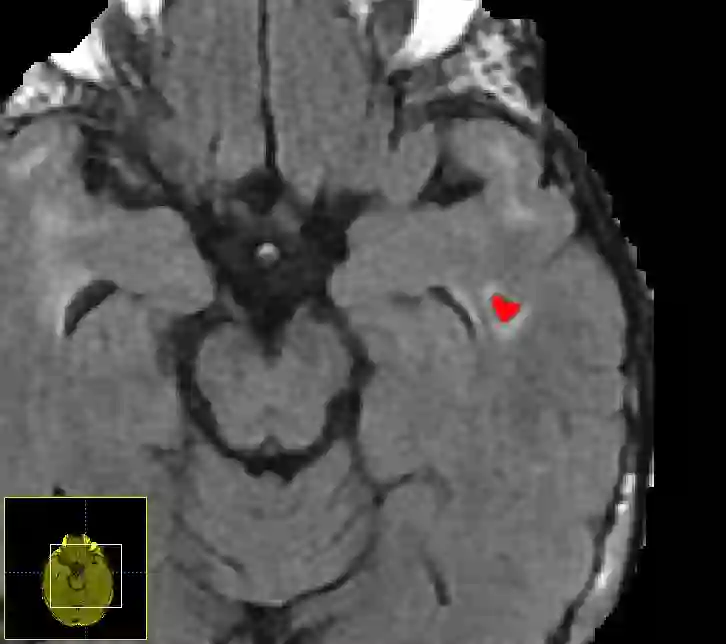

Imaging markers of cerebral small vessel disease provide valuable information on brain health, but their manual assessment is time-consuming and hampered by substantial intra- and interrater variability. Automated rating may benefit biomedical research, as well as clinical assessment, but diagnostic reliability of existing algorithms is unknown. Here, we present the results of the \textit{VAscular Lesions DetectiOn and Segmentation} (\textit{Where is VALDO?}) challenge that was run as a satellite event at the international conference on Medical Image Computing and Computer Aided Intervention (MICCAI) 2021. This challenge aimed to promote the development of methods for automated detection and segmentation of small and sparse imaging markers of cerebral small vessel disease, namely enlarged perivascular spaces (EPVS) (Task 1), cerebral microbleeds (Task 2) and lacunes of presumed vascular origin (Task 3) while leveraging weak and noisy labels. Overall, 12 teams participated in the challenge proposing solutions for one or more tasks (4 for Task 1 - EPVS, 9 for Task 2 - Microbleeds and 6 for Task 3 - Lacunes). Multi-cohort data was used in both training and evaluation. Results showed a large variability in performance both across teams and across tasks, with promising results notably for Task 1 - EPVS and Task 2 - Microbleeds and not practically useful results yet for Task 3 - Lacunes. It also highlighted the performance inconsistency across cases that may deter use at an individual level, while still proving useful at a population level.